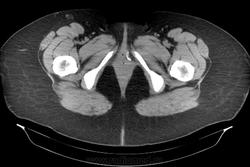

Инородное тело. Хирургическая игла.

Хирургическая игла, которую оставили гинекологи.

Да, гинекологи сами почуяли неладное и отправили пациентку на исследование. Операция была по поводу кисты левой бартолиневой железы. Со слов пациентки, ей до этого делали УЗИ, но ничего не обнаружили. Расположена она в толще большой половой губы, в преддверии влагалища.